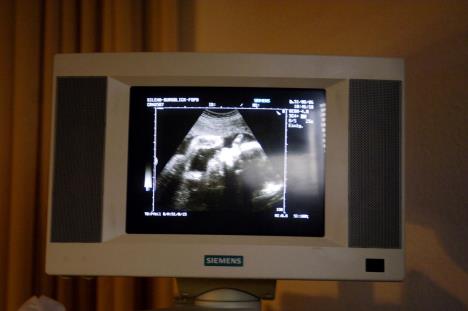

Britanka Loran Denison (27) je bila trudna sa svojim četvrtim detetom. Međutim, u 15. nedelji trudnoće redovna kontrola je pokazala da beba ima Edvardsov sindrom. Taj sindrom je redak, ali veoma ozbiljan.

Edvardsov sindrom retko je stanje i većina beba s njim ne preživi do kraja termina ili umire nekoliko sati nakon rođenja, jer imaju dodatni hromozom, broj 18. Od retkih beba koje se rode preživi samo njih 13 od 100 i to do svog prvog rođendana.

Edvardsov sindrom može da izazove niz simptoma koji se razlikuju kod različitih ljudi, uključujući poteškoće u učenju, probleme sa srcem, disajnim sistemom, bubrezima ili probavnim sistemom.